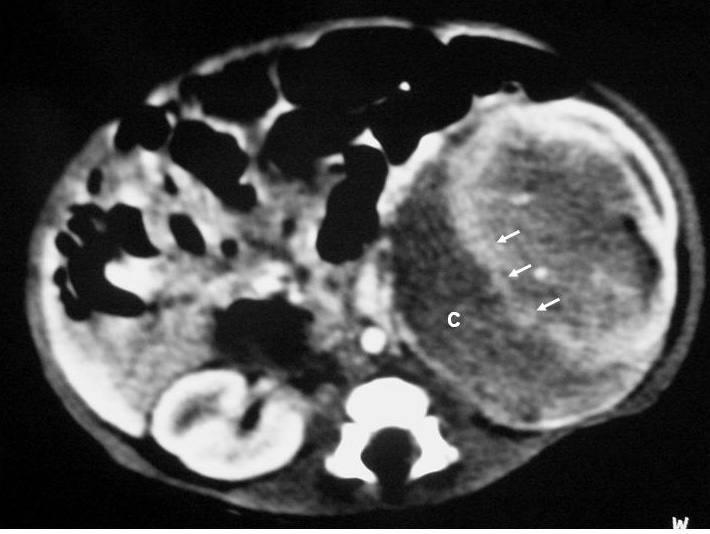

El sarcoma de células claras tuvo lugar en un niño de 2 años estudiado por masa abdominal, en el que se identificó una masa intrarrenal, de predominio necrótico y una adenopatía retrocava (fig. 8).

Fig. 8. Sarcoma de células claras. Tomografía computarizada abdominal con contraste intravenoso. Corte sobre polo inferior renal. Masa en riñón derecho, sólida, hipodensa, con gran crecimiento extrarrenal y que desplaza colon ascendente hacia delante (flechas). Adenopatía retrocava, hipodensa (A) de 3 cm.

Macroscópicamente es indistinguible del TW unilateral y único1,2,10. Es un tumor sólido, aunque hasta en un 50% puede tener quistes, no encapsulado, que infiltra, distorsiona y comprime el parénquima renal4. Puede tener áreas de necrosis y hemorragia y no suele haber invasión intravascular1,4.

Su comportamiento es muy agresivo y su pronóstico es peor que el del TW. Aunque no suele existir al diagnóstico, es muy característica la afectación metastásica del hueso, ya sea con un patrón lítico, permeativo o escleroso1,10. También puede metastatizar en los ganglios, el hígado y el pulmón. Requiere un largo seguimiento tras el tratamiento quirúrgico y quimioterápico, puesto que las metástasis pueden presentarse mucho tiempo después del tratamiento.

En el paciente de nuestra serie, con una masa renal grande, de aspecto necrótico y una gran adenopatía retroperitoneal, no se encontraron lesiones óseas asociadas. Se trató con cirugía, radioterapia y quimioterapia con buena evolución.